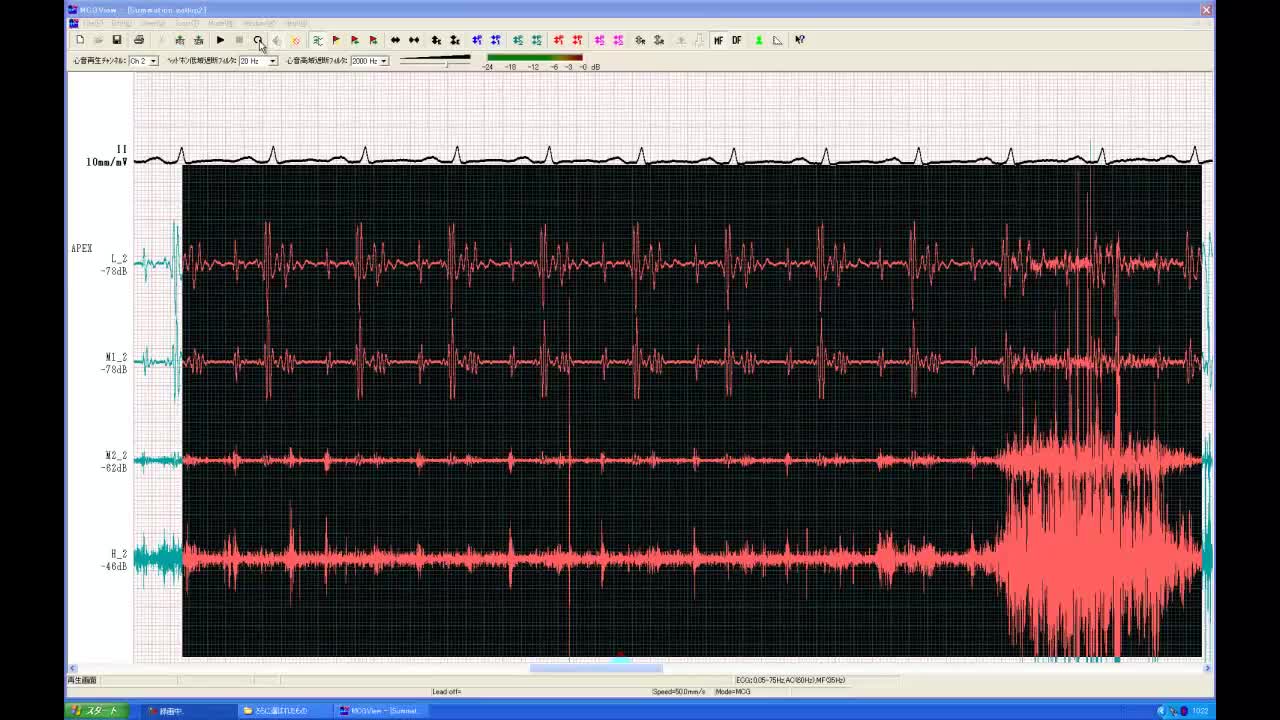

• 図7 summation gallop(重合奔馬調) a:胸骨左...

• 図7 summation gallop(重合奔馬調)a:心尖

• 図7 summation gallop(重合奔馬調) b